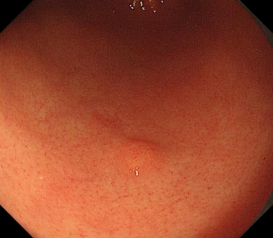

科室高清晰胃肠镜:正常的胃窦(线圈样腺管)和食管粘膜放大观察(IPCL)

消化道早癌的病例展示(经内镜手术或活检证实):

胃角的腺癌

胃窦的微小腺癌

胃窦印戒细胞癌

十二指肠降段早癌